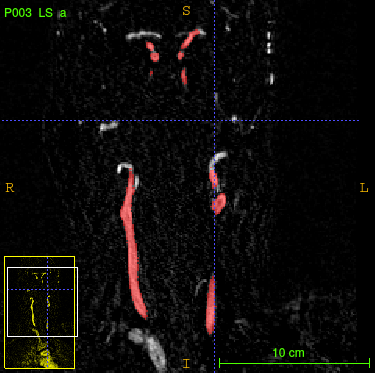

To address the drawbacks of existing approaches, we introduce a network structure which is able to generate accurate volumetric segmentation masks of very large 3D volumes. The main idea is to integrate maximum intensity projection (MIP) layers from different directions which transform the data to 2D images containing information of the full 3D image. As an example, we test the network for segmenting blood vessels (arteries and veins) in magnetic resonance angiography (MRA) scans (Figure 1.1).

We aim at generating volumetric binary segmentation masks. In particular, as one targeted application, we aim at segmenting blood vessels (arteries and veins) which assists the doctor to detect abnormalities like stenosis or aneurysms. Furthermore, the medical sector is looking for a fully automated method to evaluate large cohorts in the future. The Department of Neuroradiology Innsbruck has provided volumetric MRA scans of 119 different patients. The images face the arteries and veins between the brain and the chest. Fortunately, also the volumetric segmentation masks (ground truths) of these 119 patients have been provided. These segmentation masks have been generated by hand which is long hard work (Figure 1.1).

Our goal is the fully automated generation of the 3D segmentation masks of the blood vessels. For that purpose we use deep learning and neural networks. At the first glance, this problem may seem to be quite easy because we only have two labels (0: background, 1: blood vessel). However, there are also arteries and veins which have label 0 which might confuse the network since we only want to segment those vessels of interest. Other challenges are caused by the big size of the volumes ( voxels) and by the very unbalanced distribution of the two labels (in average, 99.76 % of all voxels indicate background).